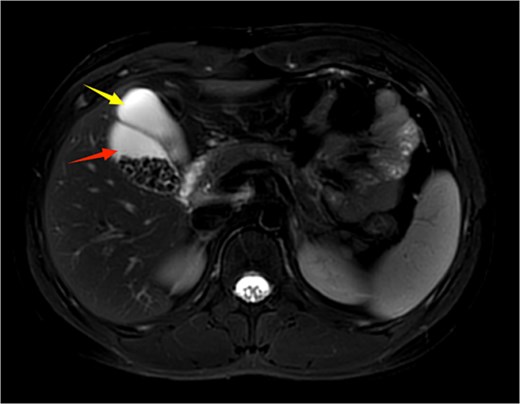

A 21-year-old male patient was admitted to our hospital with a 2-year history of intermittent right upper quadrant colicky pain. The symptoms initially occurred 2 years ago after consuming fried food, accompanied by nausea and vomiting, and were relieved after antispasmodic and analgesic treatment. Over the past 2 years, the symptoms recurred frequently, prompting the patient to seek further evaluation at our institution. The patient had no significant past medical history, including hypertension, diabetes, coronary heart disease, or other chronic conditions. He denied smoking, alcohol consumption, and any known drug allergies. Physical examination on admission revealed stable vital signs, with no jaundice observed in the skin or sclera. The abdomen was flat, with mild tenderness in the right upper quadrant and no rebound tenderness. The liver and spleen were not palpable. Murphy's sign was negative, abdominal percussion yielded tympanic sounds, and bowel sounds were normal. Laboratory tests, including complete blood count, liver function (bilirubin, ALT, AST, etc.), coagulation profile, amylase, lipase, and infection markers, were all within normal limits. Ultrasonography indicated multiple gallstones, a thickened and indistinct gallbladder wall, and suspicion of a folded gallbladder or possible double gallbladder malformation. To further delineate the biliary anatomy and ensure surgical safety, an abdominal MRI was performed. Magnetic resonance imaging (MRI) confirmed a double gallbladder malformation, with multiple stones in the lateral gallbladder (Figs 1 and 2). The clinical diagnosis was established as cholelithiasis with double gallbladder malformation.

Upper abdominal MRI demonstrates a double gallbladder variation. The two arrows indicate the respective gallbladders, the lateral one of which contains multiple gallstones.